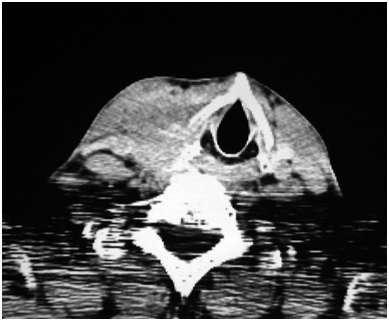

A 73year old male was admitted to our hospital because of hoarseness and a right neck nodule. From a month prior to admission, he suffered from cough and sputum, and consulted to another doctor first. He was pointed out the tumor in the right lobe of thyroid gland and the deviation of trachea on chest X-ray and CT scan of the neck and upper mediastinum (Figure 1), and he referred to our hospital for further investigation and treatment.

Figure 1 CT image of thyroid tumor before treatment.